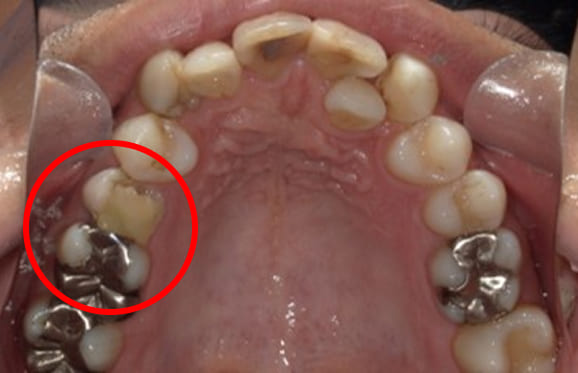

● C4を超え歯根までの虫歯を抜歯、スペースを利用して歯並び全体を整えた症例

藤沢デンタルオフィスの虫歯や破折で抜歯後の部分矯正